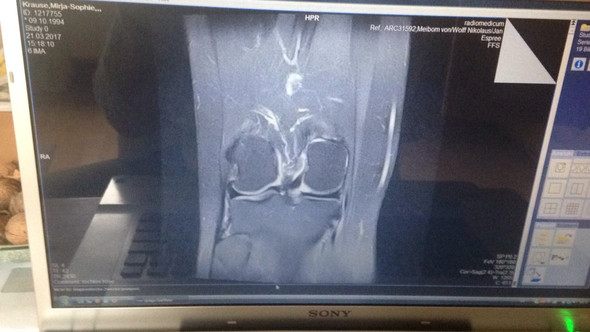

22jahre Alt Und Knorpelschade Hinter Der Kniescheibe Grad 3 4 Knie Mrt Knorpelschaden

Mit einer Knorpeltransplantation kann der verfrühte Gelenkverschleiss verhindert und die schmerzfreie Funktion des Kniegelenks wieder hergestellt werden. Knorpelschäden im Kniegelenk sind häufig. Die Wassereinlagerung Knochenmarködem hinter dem Knorpelschaden weist auf einen frischen unfallbedingten Knorpelschaden hin.

Das Herausspringen der Kniescheibe aus dem Gleitlager in Form eines akuten Ereignisses bei einer Drehbewegung ist oft höchst schmerzhaft und erfordert dann häufig eine Notfallbehandlung. Darin zeigte sich ein ausgedehnter Knorpelschaden im Bereich der Kniescheibenrückfläche Abb. Knorpelschaden hinter Kniescheibe.